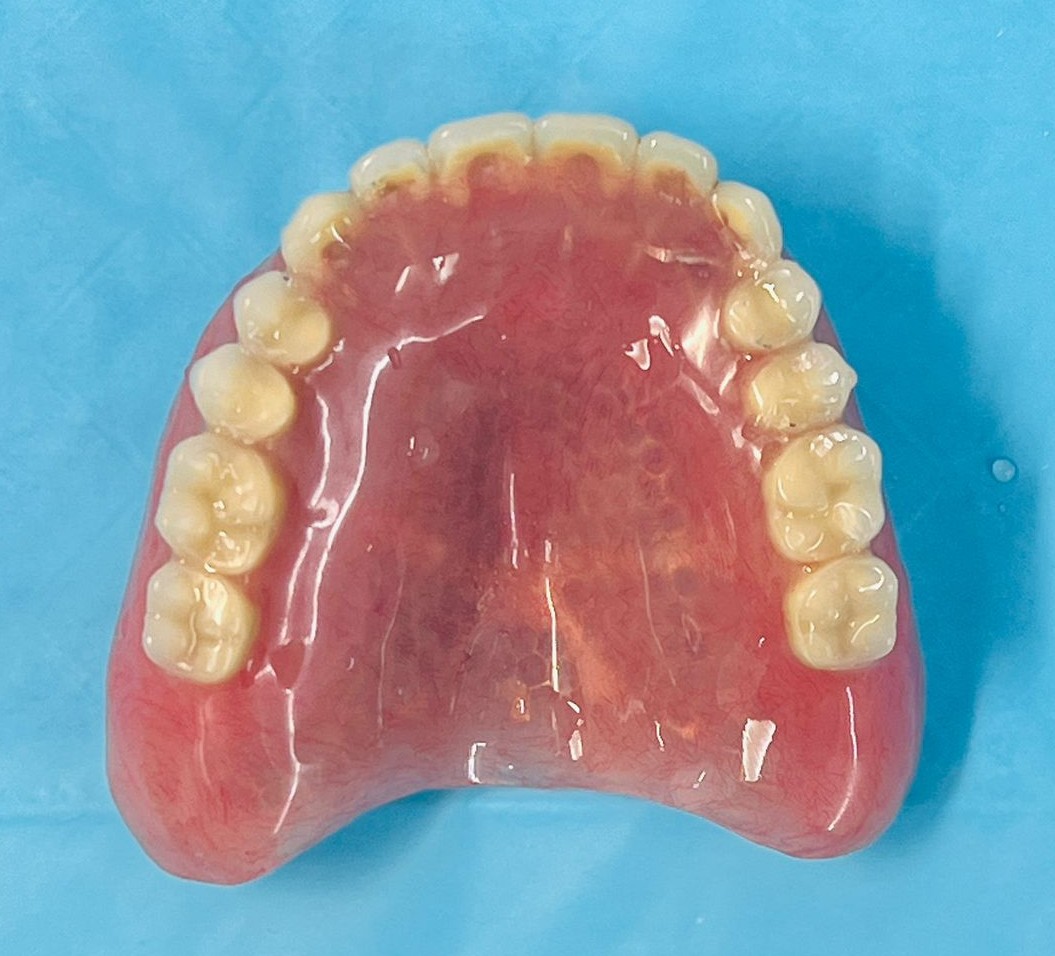

There are two types of implant dentures: bar-retained and ball-retained. In both cases, the denture will be made of an acrylic base that will look like gums. Porcelain or acrylic teeth that look like natural teeth are attached to the base. Both types of dentures need at least two implants for support.

Upper Jaw Implant Complete Dentures